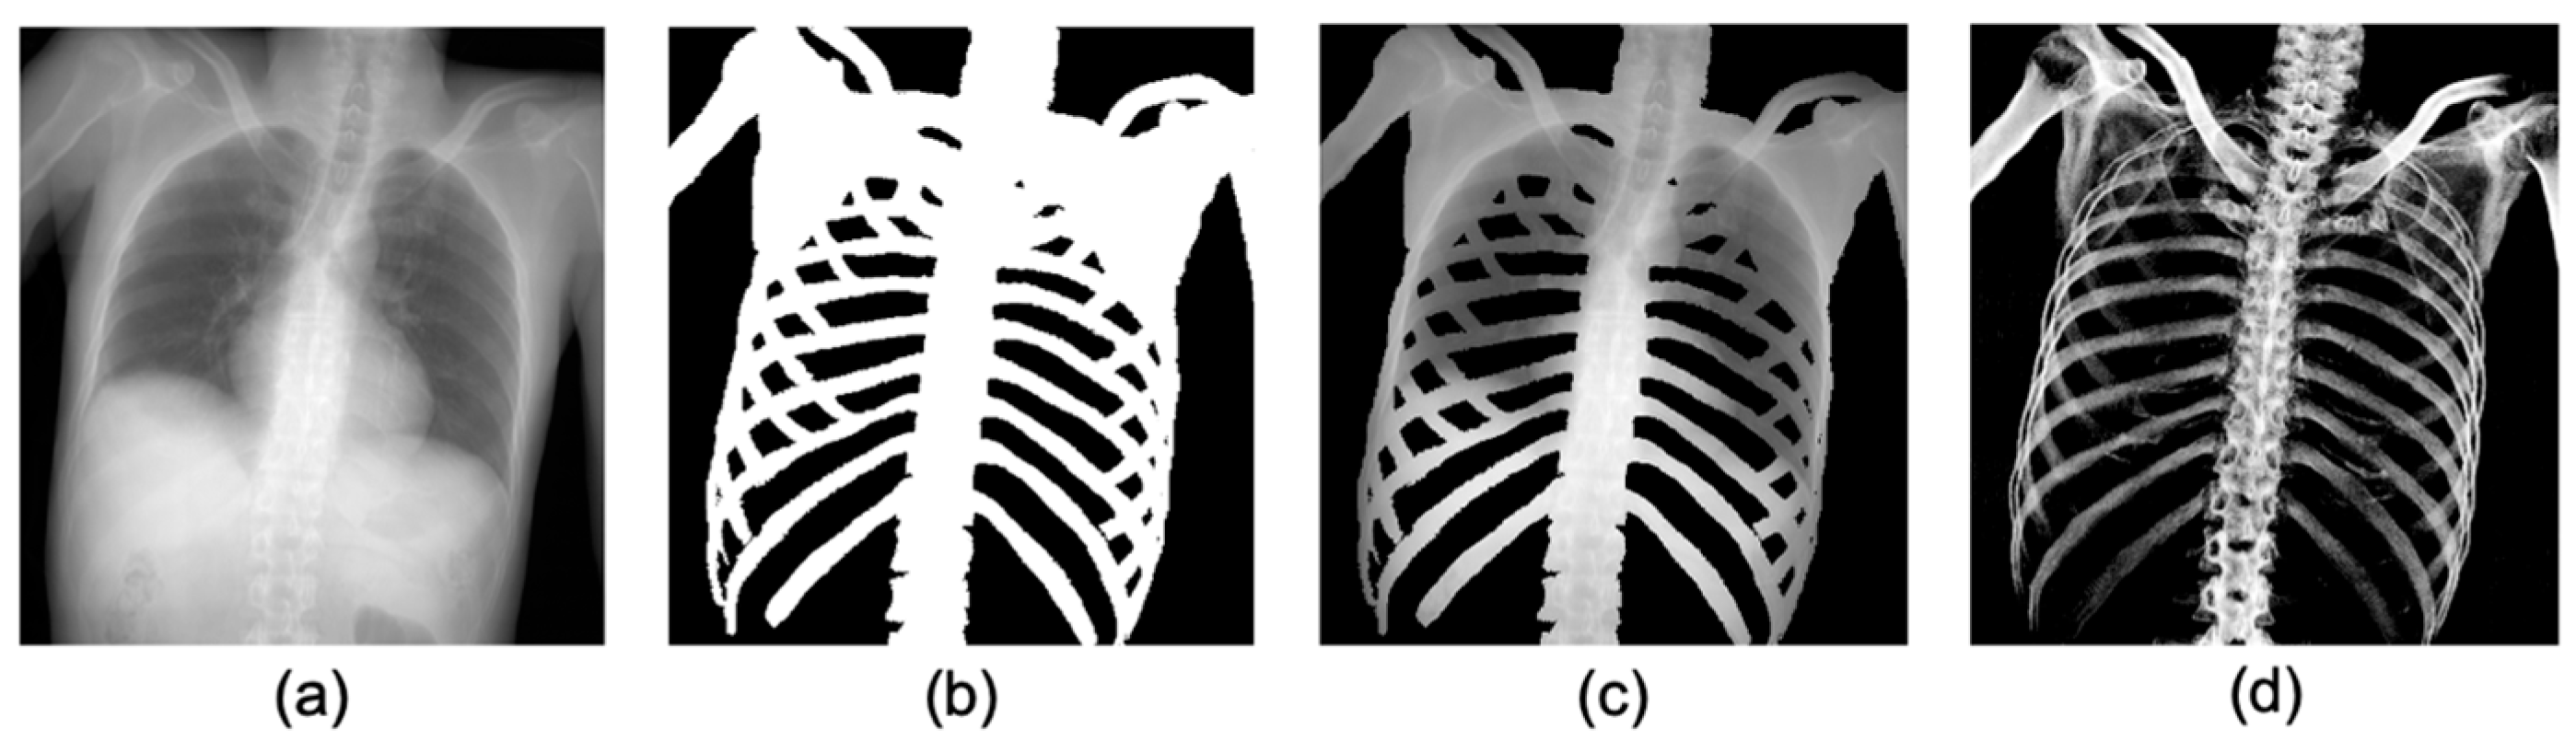

2.3. Pre-Processing: Producing Training Datasets from PMCT Images